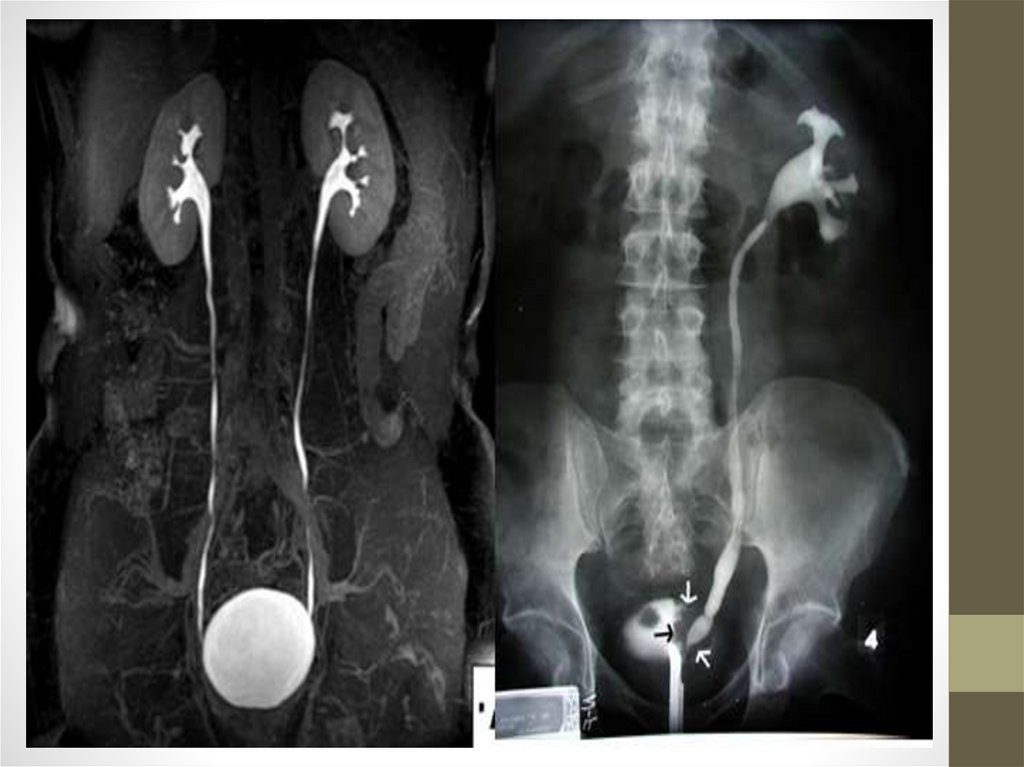

• Инструментальные: УЗИ, сканирование. КТ, МРТ,

ангиография почечных артерий.

• Функциональные методы исследования почекэкскреторная урография, моча по Зимницкому.

• Специальные исследования: УЗИ, радионуклидная ренография,

сканирование, динамическая сцинтиграфия.

• При обследовании: (рентгенологическое, УЗИ)

выявляются камни, особенно хорошо выявляются

ураты, хуже - фосфаты.

• Рентгенологическое исследование, компьютерная

томография, радиоизотопное сканирование выявляют

тени конкрементов в почках.